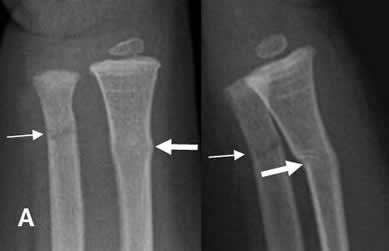

Fig 63 A. Fractura en torus.

A: y B: Rx AP. Cortical “arrugada” en el tercio distal del radio, por fracturas en torus.

Fig 63 B. Fractura en torus.

A y B: Rx AP. Fractura en torus del radio distal. En la proyección de control, se identifica imagen densa en el lugar de la cicatrización.